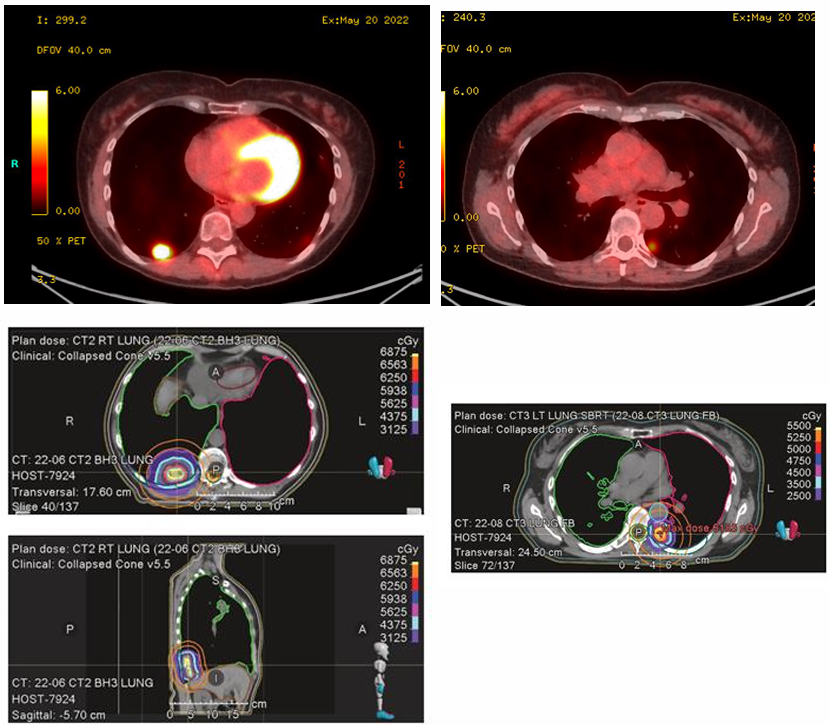

2022年6月至8月,病情再次发生演变:

肺部新发病灶:双肺下叶出现新结节。再次实施SBRT治疗(右肺下叶两处结节,62.5Gy/10次;左肺下叶一处结节 50Gy/5次)。

中枢神经系统(CNS)受累:2022年7月,患者出现言语困难。MRI发现左额叶单发巨大脑转移瘤,伴严重血管源性水肿及中线移位。

干预措施:

外科手术:于7月22日行急诊手术切除。

放射外科:8月对切除残留腔实施SRT,27Gy/3次。

ee67d7ea-efa1-4955-83e4-1454ba061da1.png